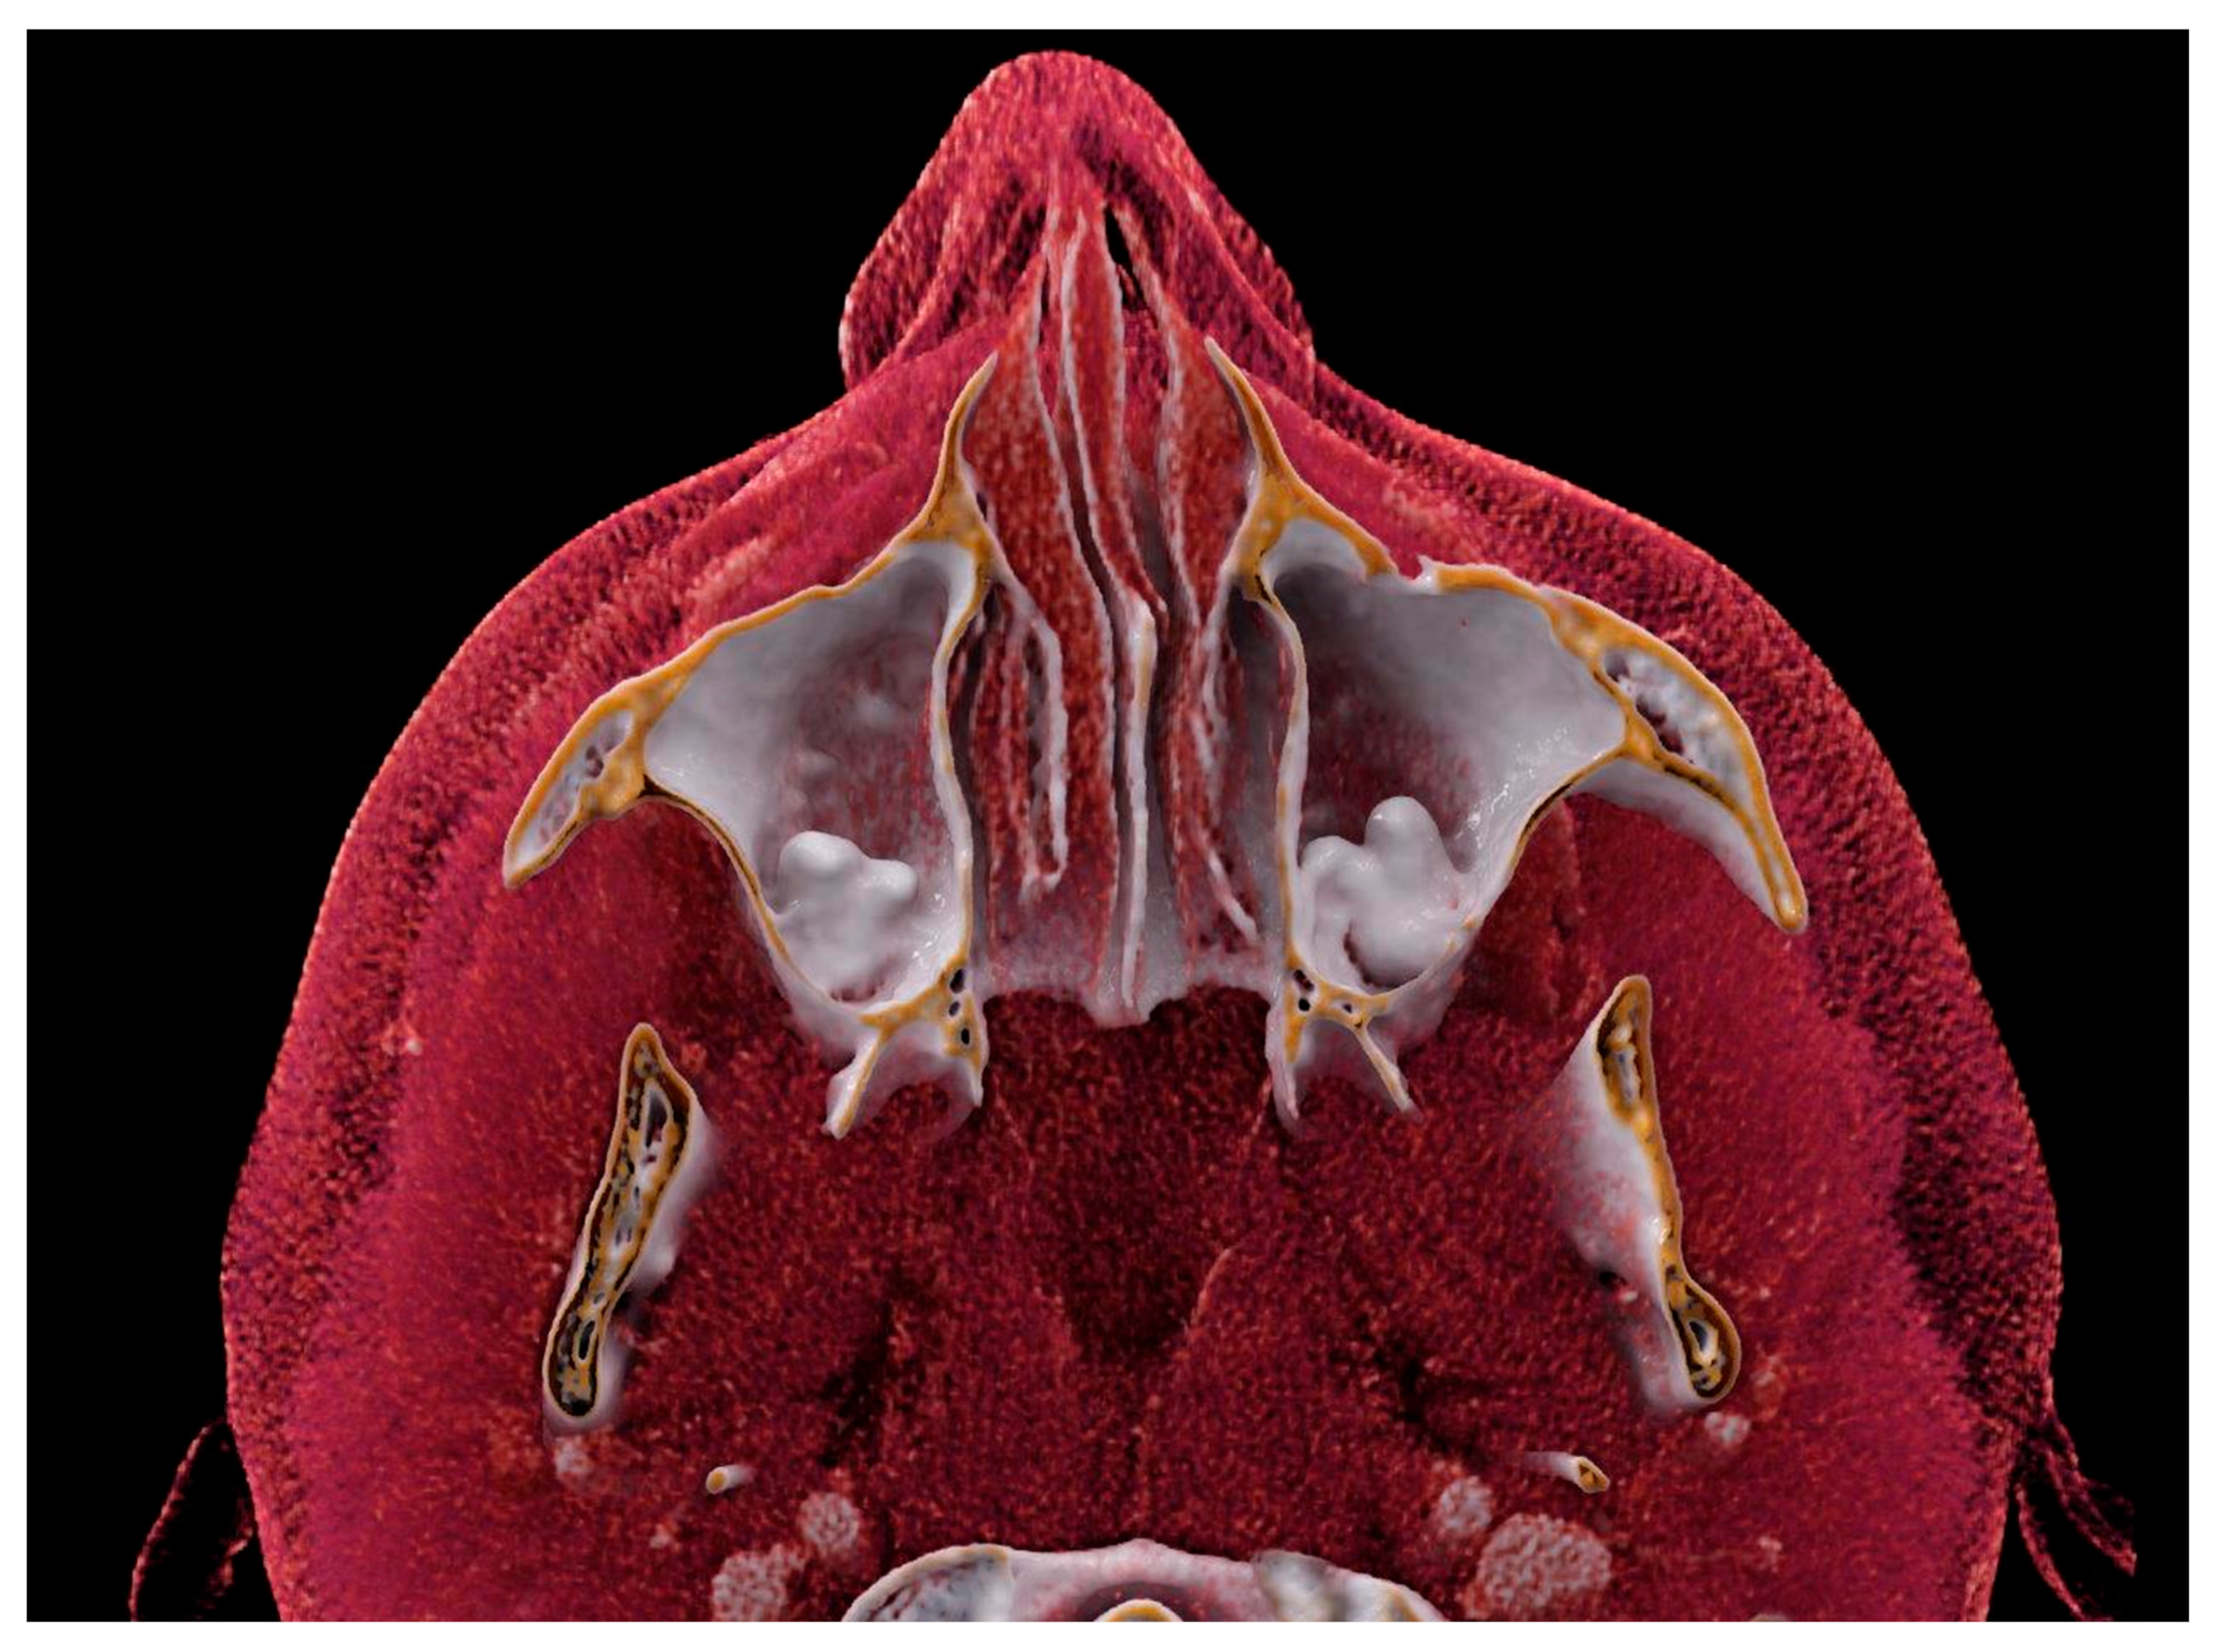

None of the reported works and cases have ever used volume rendering (VR) or CR for three-dimensional visualization of the molar in the maxillary cavity.

CT provides detailed information about the location and morphology of the ectopic tooth, as well as the evaluation of surrounding anatomical structures, facilitating treatment planning.

In the present case, CT was used to visualize the ectopic teeth in the maxillary sinus. CT has been widely used to diagnose ectopic teeth in the maxillary sinus because it can provide detailed information about the location and morphology of the ectopic tooth. In addition, CT allows evaluation of the surrounding anatomical structures, such as the sinus walls and adjacent teeth, in light of a possible surgical treatment, facilitating its planning [

We also used cinematic rendering to visualize the ectopic teeth in the maxillary sinus. By simulating the propagation and interaction of light beams as they move through the volumetric data, cinematic rendering creates a representation of 3D pictures that is more lifelike than that produced by ordinary volume rendering [

11]. In general, cinematic rendering uses the same procedures as volume rendering to determine color and opacity: transfer functions are employed to convert the gray values in each voxel of the original pictures to a color and opacity value. Afterward, a variety of transfer functions can be used for rendering, based on the case’s features and the structures that should be highlighted. However, the algorithm used in cinematic rendering is based on path-tracing techniques and the global illumination model, which simulate the various paths that billions of photons traveling from all possible directions take through a volumetric dataset and their interaction with the volume to form one pixel. This is in contrast to ray casting techniques, in which each pixel is formed by one light ray. As a result, this recently introduced 3D reconstruction technique provides more realistic 3D images with high spatial resolution and excellent tissue differentiation. Just like VR, CR can offer insights into various tissue types by adjusting the display parameters to enhance the visualization of soft tissues compared to denser structures. CR’s shadowing capabilities can enhance our understanding of anatomy, especially in areas with complex structures, including those with overlapping or protruding elements. However, it is worth noting that the prospective view in CR may partially obscure deeper regions.

In contrast to traditional VR, which treats each reconstructed voxel independently, CR presents neighboring voxels interactively. This adaptability allows for the manipulation of lighting and shadow conditions in a panoramic view. Furthermore, in addition to shadowing, CR’s global lighting model excels at revealing intricate anatomical details, making it particularly useful for visualizing small structures [

Overall, the use of CT and film rendering in our case allowed us to accurately diagnose and localize the ectopic teeth in the maxillary sinus. These imaging modalities are valuable tools in the diagnosis and management of ectopic teeth in the maxillary sinus and may aid in the planning of surgical interventions [